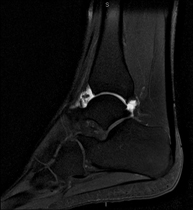

- Ankle MRI

Examination to study the joint and its frequent ligament injuries (sprains) as well as damage to other structures such as cartilage or bone. It is also very useful for diagnosing disorders of the Achilles tendon (tendinitis, ruptures). Duration: approximately 20 minutes. It is a radiation-free procedure.